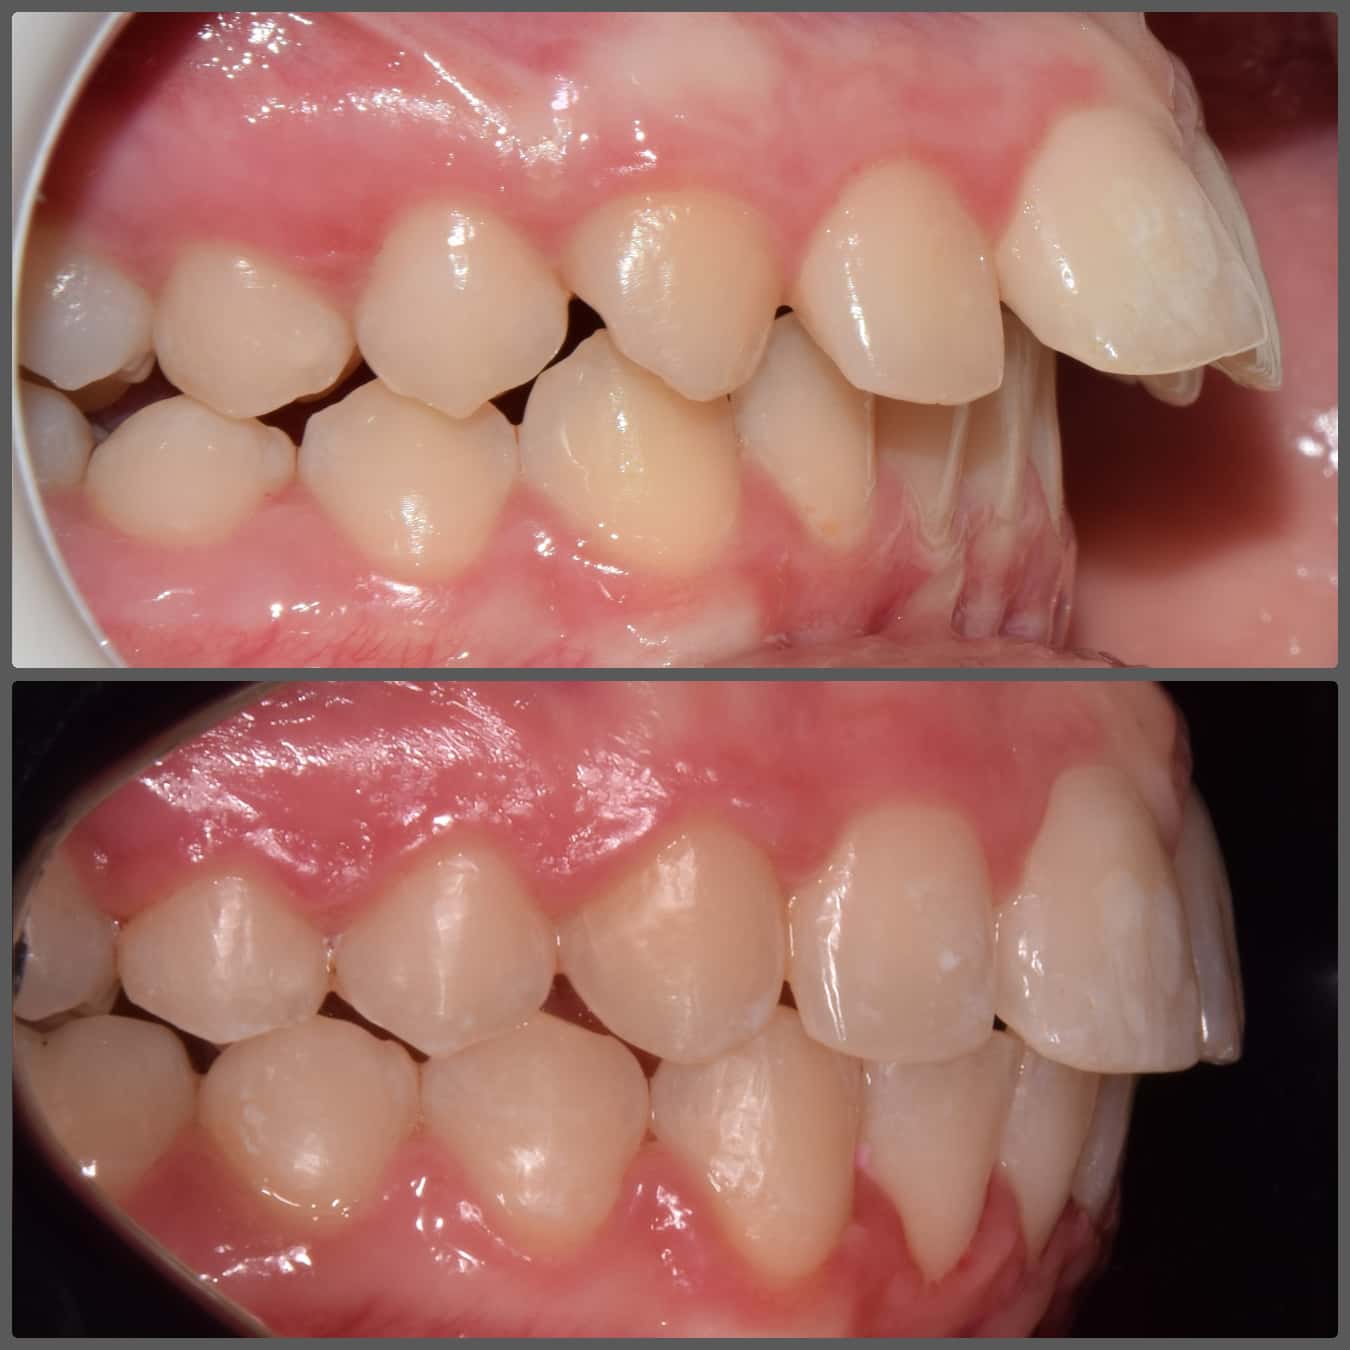

Extrém súlyos alsó-felső torlódása miatt jött hozzám fogszabályozási konzultációra Viki. A korábbi szakvélemények mindegyike foghúzással járt volna. Súlyosan eltolódott alsó-felső középvonalat, súlyos alsó-felső torlódást, mélyharapás, fogívszűkületet és a nyelv felé dőlő fogíveket diagnosztizáltam. Viki harapási és anatómiai adottságai miatt úgy ítéltem meg, hogy a kezelését foghúzás nélkül is végig tudjuk vinni. H4 önligírozó fogszabályzó készüléket ragasztottunk Vikinek, és a torlódott területeken tolórugóval csináltunk helyet a fogívből kiszorított fogaknak. A harapás harmonizálást és a mélyharapás korrekcióját intermaxilláris gumihúzással, valamint harapásemelőkkel végeztük. A teljes kezelés 26 hónapig tartott, melynek végére egy igazán gyönyörű, telt mosolyt sikerült Viki arcára varázsolni, mindemelett a szinte tökéletes oldalsó fogilleszkedést is megtartottuk, tovább javítottuk. Az ilyen látványos változások, páciens átalakulások miatt szeretem a legjobban a munkám!